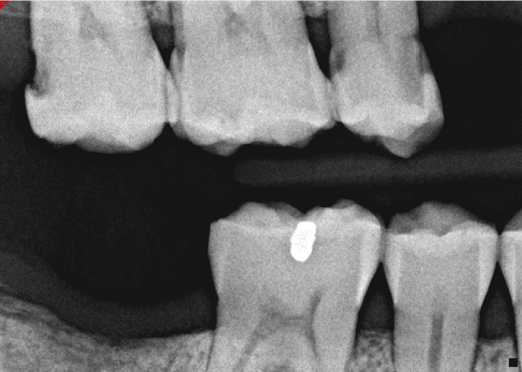

A 42-year-old male patient with a unremarkable health history presented in the AEGD Residency Program clinic with a chief complaint of pain in the mandibular right posterior area. Fig- ure 30 shows an unremarkable occlusal view of tooth No. 29; however, the radiograph showed deep distal caries near the root canal (Figure 31). Several treatment options were discussed with the patient, including extraction, root canal therapy, post and crown, and a distal occlusal composite that would later serve as a "margin elevation" material following endodontic therapy and preparation for a distal occlusal ceramic inlay or onlay. The patient chose the latter option.

Fig 31. Preoperative radiograph showing deep caries in canal. Restoration prior to endodontic therapy is required.

Figure 31